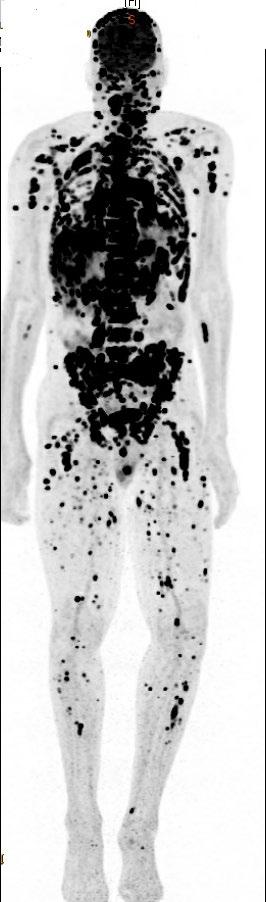

Trends in MM Natural History by Race

MM Incidence  Higher incidence in AA vs White patients:

• 15.9 vs 7.5 cases per 100,000 per year

MM Mortality  Higher mortality in AA vs White patients:

• 5.6 vs 2.4 MM deaths per 100,000

 5-year relative survival evolution from 1973 to 2005

The expected survival is nearly 10 years for all patients, but still less than 5 years in patients with high risk disease

MM Survival

• Survival for White patients increased significantly from 26.3% to 35%

• Survival for AA patients increased from 31% to 34.1%